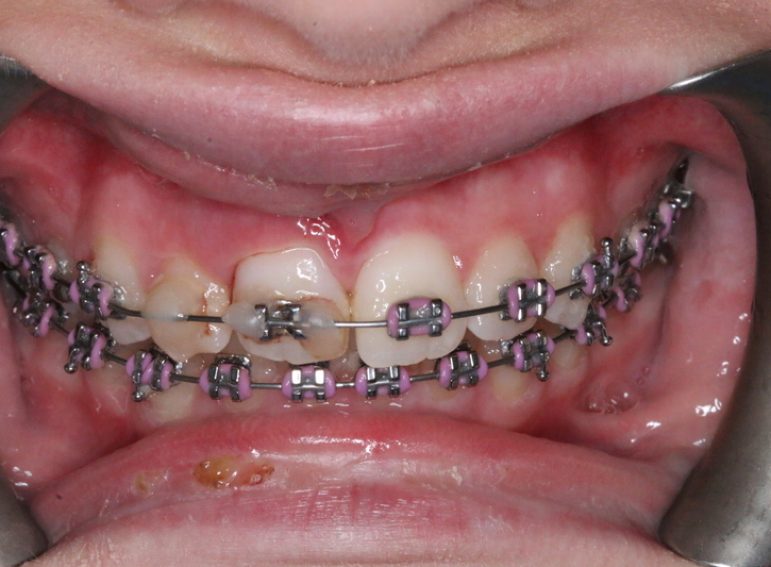

Case 5 – Dental Trauma

Severe Intrusion during braces